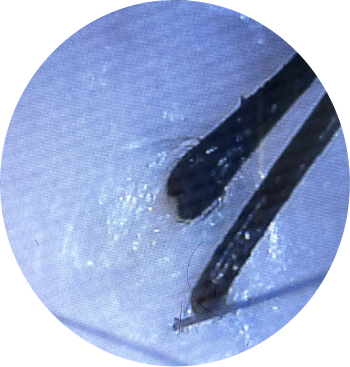

Gary’s scalp condition was caused by head lice, which developed due to consistently undried hair and poor scalp hygiene. This neglect led to severe irritation, infection, and patchy hair loss, with noticeable clumps of hair falling out.

• Lice Removal and Scalp Cleansing: A thorough cleansing process was carried out to remove lice and their eggs, ensuring the scalp was disinfected and free from infestations.